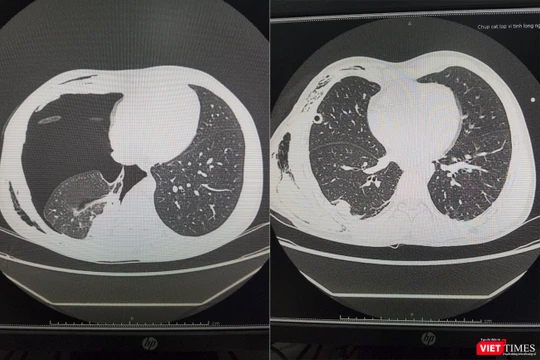

VietTimes -- Bằng sự trợ giúp từ các chuyên gia Bệnh viện Hữu nghị Việt Đức qua hệ thống Telemedicine, Bệnh viện Đa khoa tỉnh Quảng Ninh đã cứu sống bệnh nhân trong tình trạng nguy kịch do tràn khí màng phổi tái phát do vỡ kén khí màng phổi.